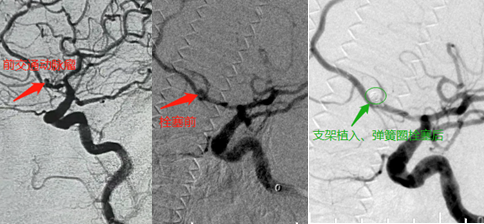

1例患者为71岁女性,有高血压史,因“急性脑梗死”入院,平时有间断性头痛,头颅MRA可疑前交通动脉瘤,全脑血管造影(DSA)证实前交通动脉宽颈囊形动脉瘤,大小约2.6mm*2.9mm经过讨论,并向患者及家属充分告知,选择支架辅助弹簧圈栓塞方案。该方案是将弹簧圈送至动脉瘤腔,使动脉瘤与血液循环阻隔,从而闭塞动脉瘤。在弹簧圈填塞过程中将支架置于动脉瘤颈部,起到支撑及防止弹簧圈脱落、移位的作用。本例患者于大脑前动脉植入3mm*21mm 自膨支架1,瘤体内填充3mm*4cm1mm*2cm1mm*1cm弹簧圈各1枚,术后造影示瘤体填充致密,未见造影剂滞留。麻醉醒后无不适,顺利出院。